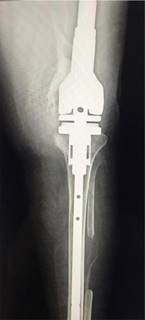

After this event, due to the spread of the infection, a left knee prosthesis was placed (Figures 1 and 2); however, due to the persistence of high levels of CRP, an intra-operative biopsy was performed, where Enterococcus faecalis was identified and acid-fast bacilli were observed, thus reaching the diagnosis of bone tuberculosis. The patient was started on amoxicillin and was referred to the outpatient service of the same institute for anti-tuberculosis treatment. The intensive phase of the treatment began with pyrazinamide, ethambutol hydrochloride, rifampicin and isoniazid (DOTBAL), taking 4 Tablets every 24 hours for 10 weeks, followed by the support phase, taking 2 Tablets every 48 hours (Monday, Wednesday and Friday) for 10 months.